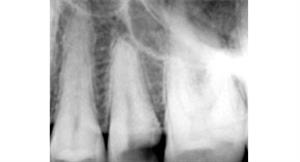

Root Canal Treatment

Before

After

A root canal procedure (endodontic treatment) is often required to save an infected tooth. Bacteria can enter a tooth through a cavity or a damaged filling. When this happens, the tooth can become abscessed, meaning the pulp inside the tooth becomes infected. An abscessed tooth can be quite painful and cause swelling in the surrounding gum tissues. If left untreated, it can cause several oral health problems. A root canal procedure removes the infected pulp and any other infected tissues within the tooth.